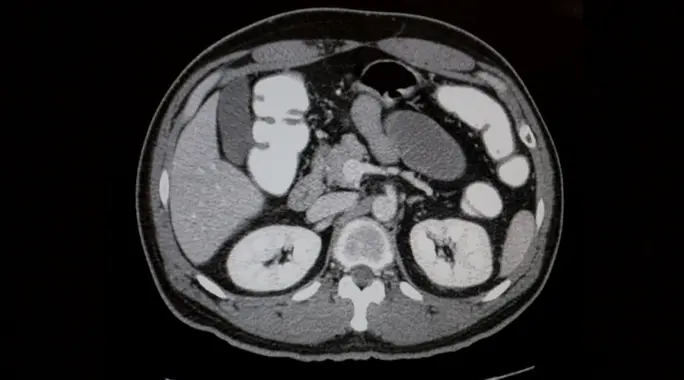

تُعد الأشعة المقطعية للبطن أداة تشخيصية قوية وغير جراحية، تستخدم سلسلة من الأشعة السينية لإنشاء صور مفصلة وعالية الدقة للأعضاء والأوعية الدموية والعظام في منطقة البطن. إنها تقدم رؤى قيمة تساعد الأطباء في تشخيص مجموعة واسعة من الحالات الصحية.

استخدامات الأشعة المقطعية للبطن

تتنوع الأسباب التي قد تدعو الطبيب لطلب الأشعة المقطعية للبطن، حيث تلعب دورًا حيويًا في تشخيص العديد من الحالات. من أبرز استخداماتها:

خطوات إجراء الأشعة المقطعية للبطن

يستغرق إجراء الأشعة المقطعية للبطن عادةً من 10 إلى 30 دقيقة. يتضمن الفحص خطوات بسيطة ومحددة لضمان الحصول على صور دقيقة وواضحة: